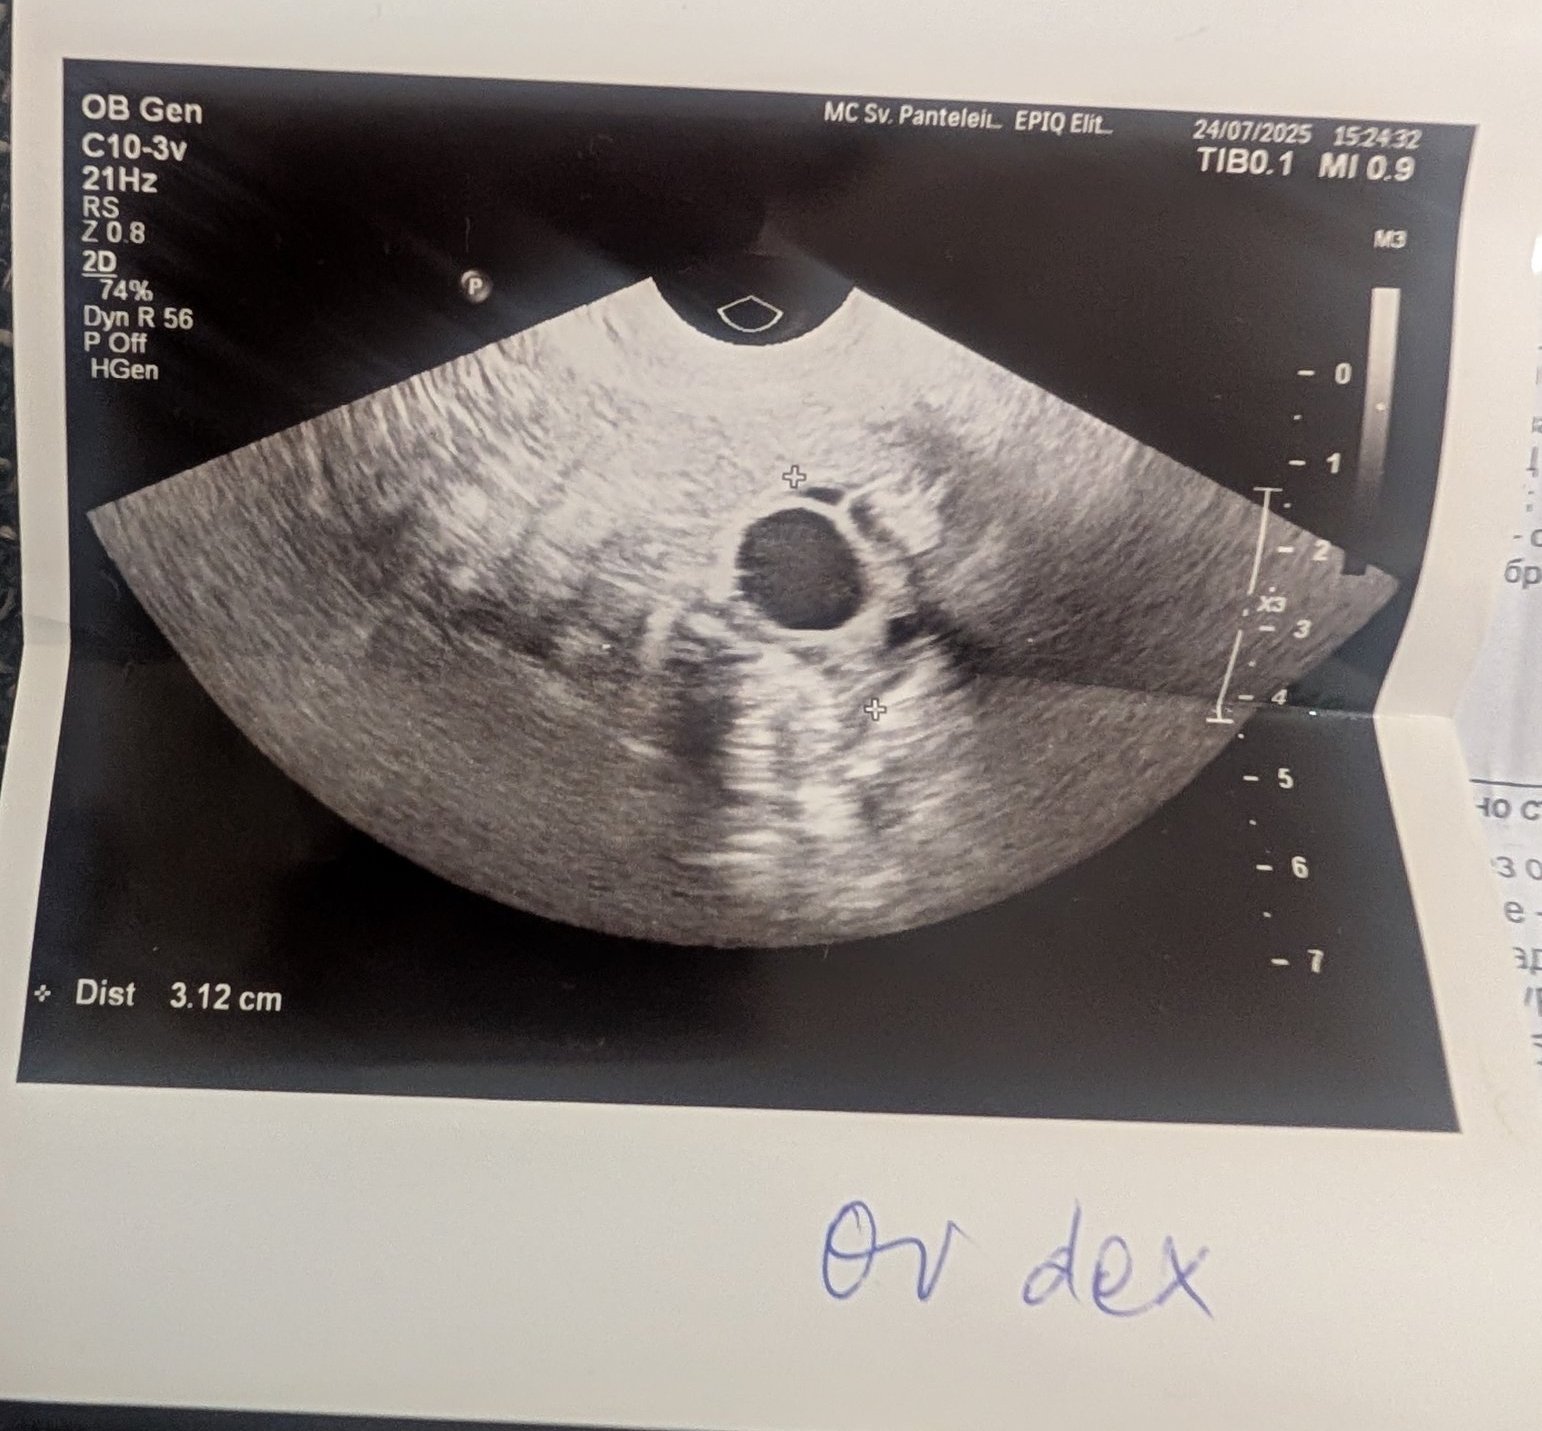

Какво представлява жълтото тяло на ехографската снимка?

-